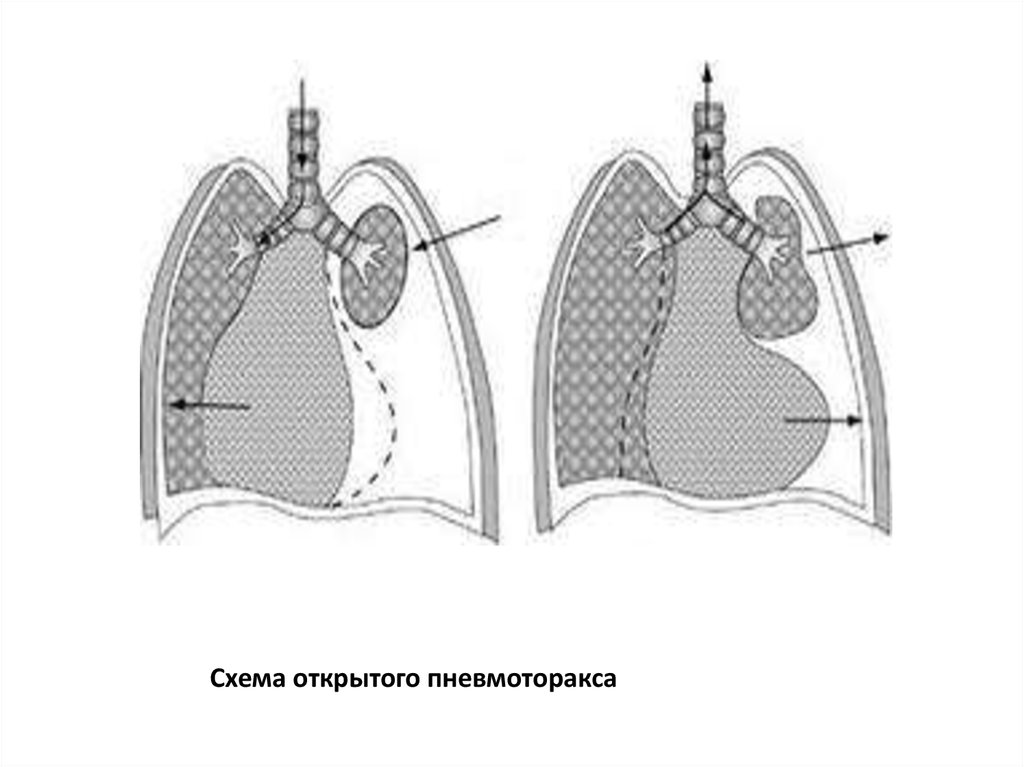

Схемы дыхания: Пневмоторакс на изображениях